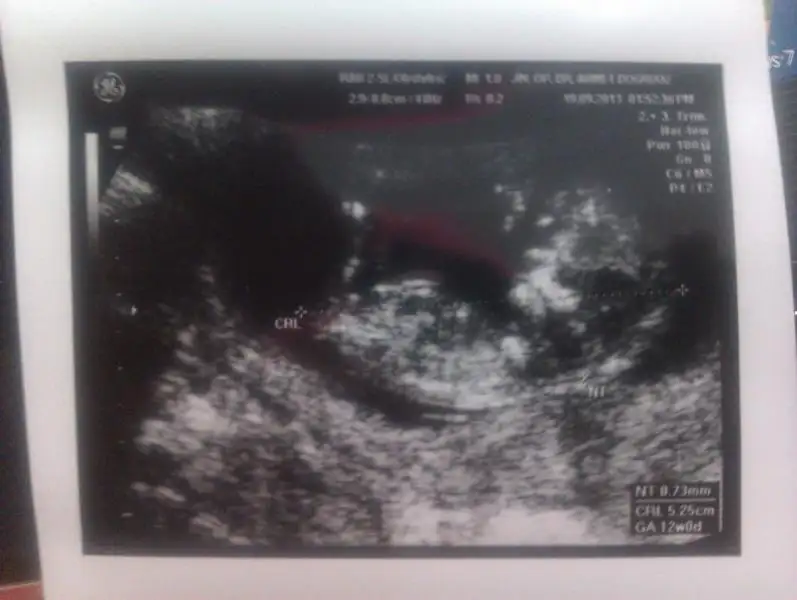

12+4 ultrason görüntüsü Eki Görüntüle 809800